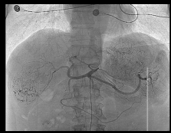

Hình 1. Quá trình nút mạch khối u gan hai bên lần 1 |

Hình 3. Quá trình nút mạch khối u gan hai bên lần 2 |

Hình 4. Quá trình nút mạch khối u gan hai bên lần 3 |